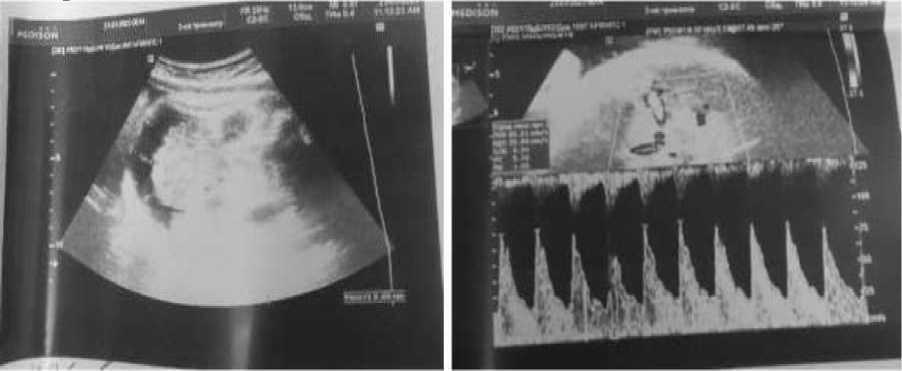

На 28-й неделе беременности пациентка вновь обратилась к врачу-терапевту женской консультации по поводу жалоб на температуру до 39 °C. В ходе сбора анамнеза было выяснено, что в течение последних двух недель была в контакте с больным ребенком (ОРВИ). В ходе АУО было выявлено тазовое предлежание плода. ВПС плода по типу тетрады Фалло, кардиомегалия (гипертрофия миокарда обоих желудочков, умеренное количество жидкости в полости перикарда), двусторонний гидроторакс, асцит. Ультразвуковые признаки неиммунной водянки плода. Осложнения: фетоплацентарная недостаточность. Многоводие (рис. 2).

Рис. 2. Фотофиксация изображений АУО плода на 28-й неделе беременности

Расширен микробиологический скрининг. В ходе исследования на вирусные инфекции было выявлено наличие антител к капсоидному антигену вируса Эпштейна – Барр (в количестве 67,58 копии) и наличие антител к парвовирусу В-19 (в количестве 7,97 копии). Выявленную у плода неиммунную водянку (асцит, двусторонний гидроторакс, гидроперикард) было решено расценивать как осложнение, вызванное инфекцией ВЭБ. Было проведено лечение полусинтетическими пенициллинами и противовирусным препаратами с иммуномодулирующим действием. Учитывая стабильное состояние плода, показания для досрочного родоразрешения отсутствовали.